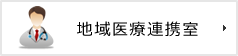

MRI検査とMRA検査

◆MRI検査

磁気共鳴診断装置(Magnetic Resonance Imaging)のことです。強い磁石と電波によって脳・脊髄をさまざまな角度で輪切りにして画像にする診断機器です。MRI は、CT に比べると時間が長くかかりますが、より詳細な情報を得ることができます。放射線による「被ばく」がありませんが、大きな音がします。ペースメーカーをつけた方は検査を出来ません。 またMRI 装置は内部が狭く、閉所恐怖症の方は検査がつらい場合があります。検査中、具合が悪くなったり、不安になったらいつでも申し出て下さい。